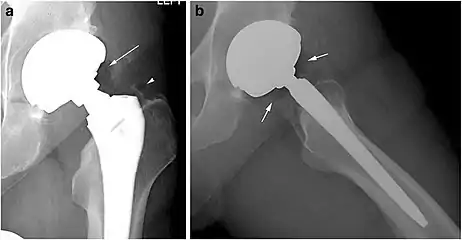

X-ray of a hip with hip replacement and pneumarthrosis, in this case aseptic.

Pneumarthrosis is the presence of air in a joint. Its presentation on radiography is a radiolucent cleft often called a vacuum phenomenon, or vacuum sign.[7] Pneumarthrosis is associated with osteoarthritis and spondylosis.[8]

Pneumarthrosis is a common normal finding in shoulders[7] as well as in sternoclavicular joints.[9] It is believed to be a cause of the sounds of joint cracking.[8] It is also a common normal post-operative finding at least after spinal surgery.[10] Pneumarthrosis is extremely rare in conjunction with fluid or pus in a joint, and its presence can therefore practically exclude infection.[8]